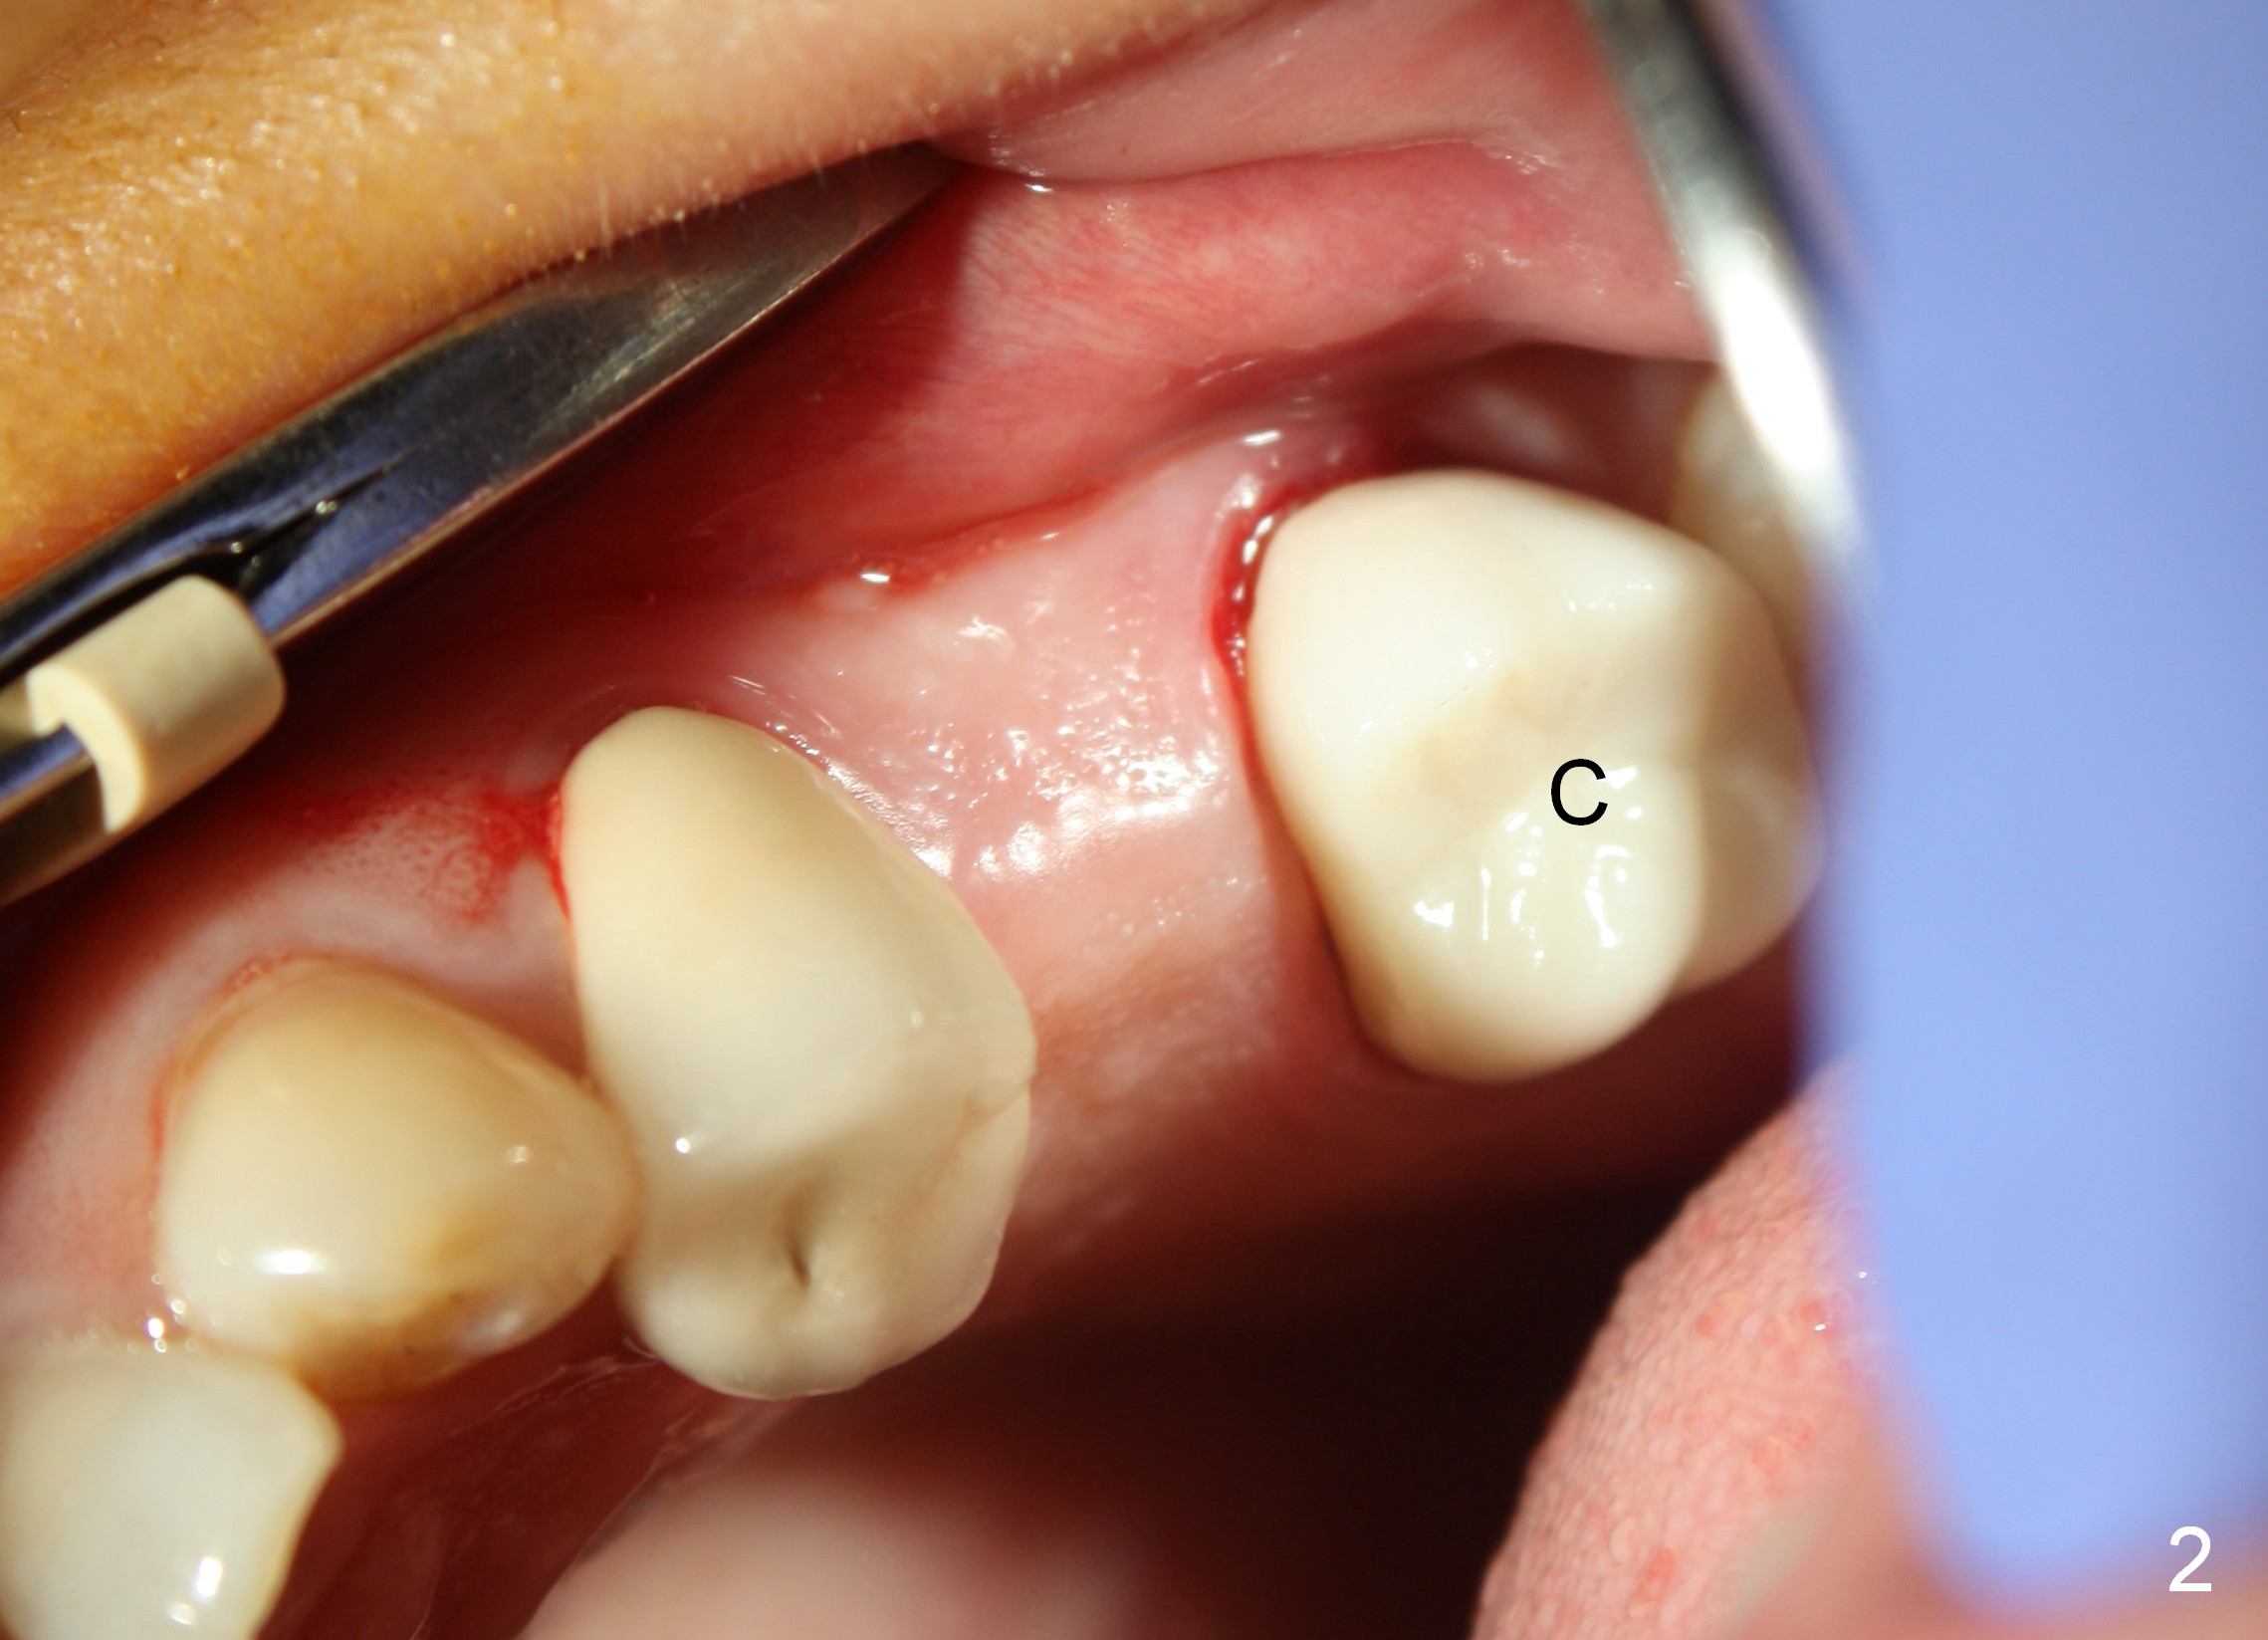

D2 Bone in Upper Bicuspid Edentulous Area

A 45-year-old lady is nervous about dental treatment. The missing tooth #13 was replaced by a 3-unit bridge. The latter is sectioned because the posterior abutment has caries. PA in Fig.1 is taken when root canal therapy and build up are finished. Fig.2 shows the wide edentulous area with a single-unit crown being tried in for #14. Osteotomy is initiated with the crown in place without cementation, since it is easy to determine the mesiodistal position (Fig.3 red lines). Without the crown in place, osteotomy tends to be distal. In this case, the osteotomy is later attempted to be moved distally with Lindamann bur and deepened to 14 mm from the gingival margin (Fig.4). A 2.5 mm reamer is being used at 50 RPM to increase osteotomy with difficulty. Drills have to used at high RPM instead (Fig.5 4x14 mm). A 4.5x14 mm tissue-level implant is placed with insertion torque >60 Ncm (Fig.6 I); a 4x3 mm abutment (A) is placed immediately for an immediate provisional. Fig.7 is taken 7 days postop to show the gingival recipient site formed by the provisional. The patient is so afraid of X-ray that the next one is taken 1.5 years post cementation (Fig.8). It appears that dense bone bundle forms between the crest and the 1st implant thread (adaptation functional change, arrowheads). The bone density continues to increase 2 years 8 months post cementation (Fig.9 *, 10); the bone has grown into the area between the 1st 2 threads (arrow).